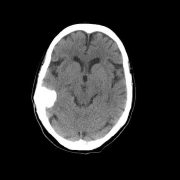

大脑镰旁钙化型脑膜瘤案例一则,脑膜瘤是较常见的良性外脑病变之一,占成人颅内肿瘤的10%至20%。钙化、骨化、骨侵犯、骨浸润和成骨细胞增生是这些肿...